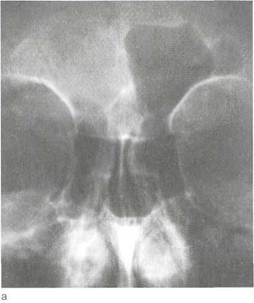

Пункцию верхнечелюстной пазухи выполняют как с диагностической, так и с лечебной целью. В настоящее время эта пункция, проводимая с лечебной целью, является наиболее популярным и эффективным способом эвакуации гнойного содержимого при воспалении верхнечелюстной пазухи (рис.

| Рис. 2.24. Пункция верхнечелюстной пазухи, а — расположение иглы под нижней носовой раковиной; б — схема тока жидкости при пункции. |